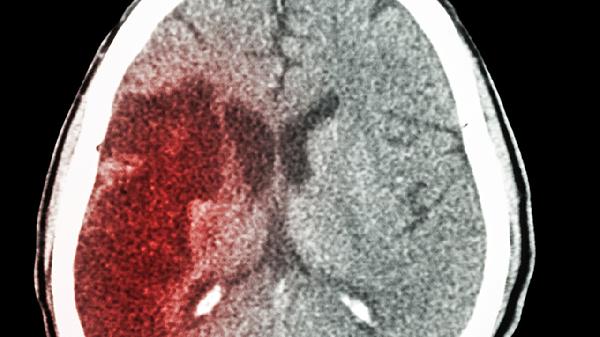

2、增加脑梗风险

长期熬夜会导致血管收缩异常,这是很多突发性脑梗的诱因之一。